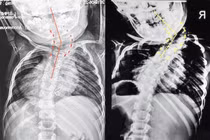

Bỏ qua thời điểm vàng can thiệp, bé 6 tuổi vẹo cột sống lệch đầu Sức khoẻ 360 14/07/2022 11:11 Bé trai bị vẹo cột sống bẩm sinh không điều trị, đến nay 6 tuổi đầu lệch sang một bên, tình trạng nặng rất khó phẫu thuật.